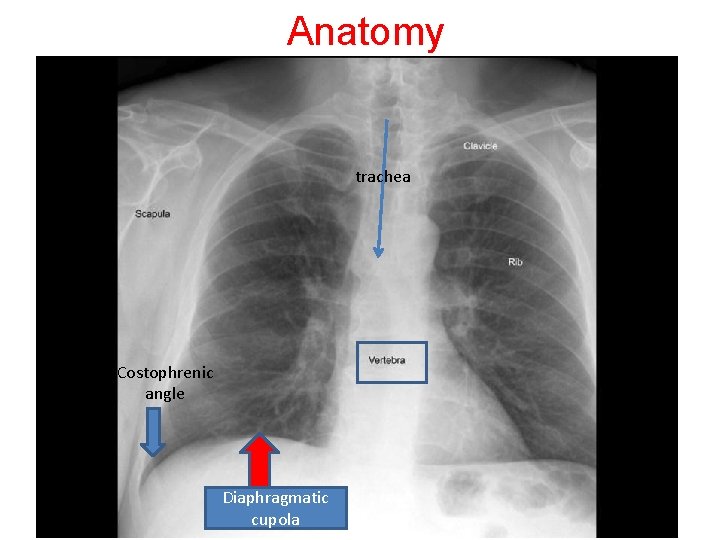

PPT CHEST X RAY ANATOMY AND PROJECTIONS PowerPoint Presentation, free Cost Phrenic Angle Other causes of costophrenic angle blunting include lung disease in the region of the costophrenic angle, and lung hyperexpansion. normal cp angle measures approximately 30°. costophrenic recesses and angles. The costophrenic angles are formed by the points at which the chest wall and diaphragm meet. pleural effusions are not the only cause of blunt costophrenic angles. Blunting. Cost Phrenic Angle.